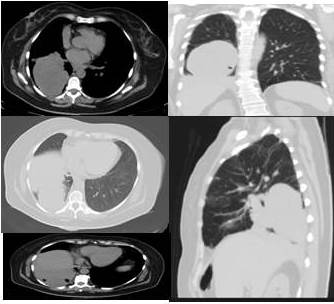

La tomografía computarizada de tórax reporta lesión de tejido blando ovalada de contorno parcialmente definidos con contacto pleural, la cual mide 9,8 cm x 8,5 cm, con engrosamiento intersticial difuso bilateral con bandas atelectásicas en el lóbulo inferior. Lesión nodular de 1 cm ubicada en el lóbulo medio (Figura 2). La tomografía de abdomen no reveló ni lesión ocupante de espacio ni enfermedad metastásica.

En vista de estos resultados y por el incremento de la sintomatología de disnea a pequeños esfuerzo, tos persistente, taquicardia, y la aparición de disfagia, se solicita control radiológico previo al ingreso en donde se evidencia en la radiografía tele de tórax posteroanterior atelectasia pulmonar total del pulmón derecho producto de la compresión por la gran lesión tumoral, así como del material mixoide (gelatinoso) que produce este tipo de pulmón el cual posiblemente este inundando al trato bronquial principal derecho (Figura 3).